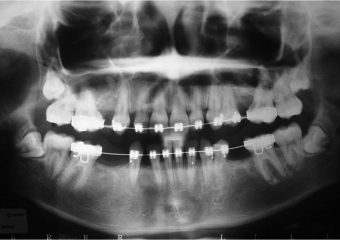

Raio após implantes instalados

Raio x após dentes provisórios fixos instalados